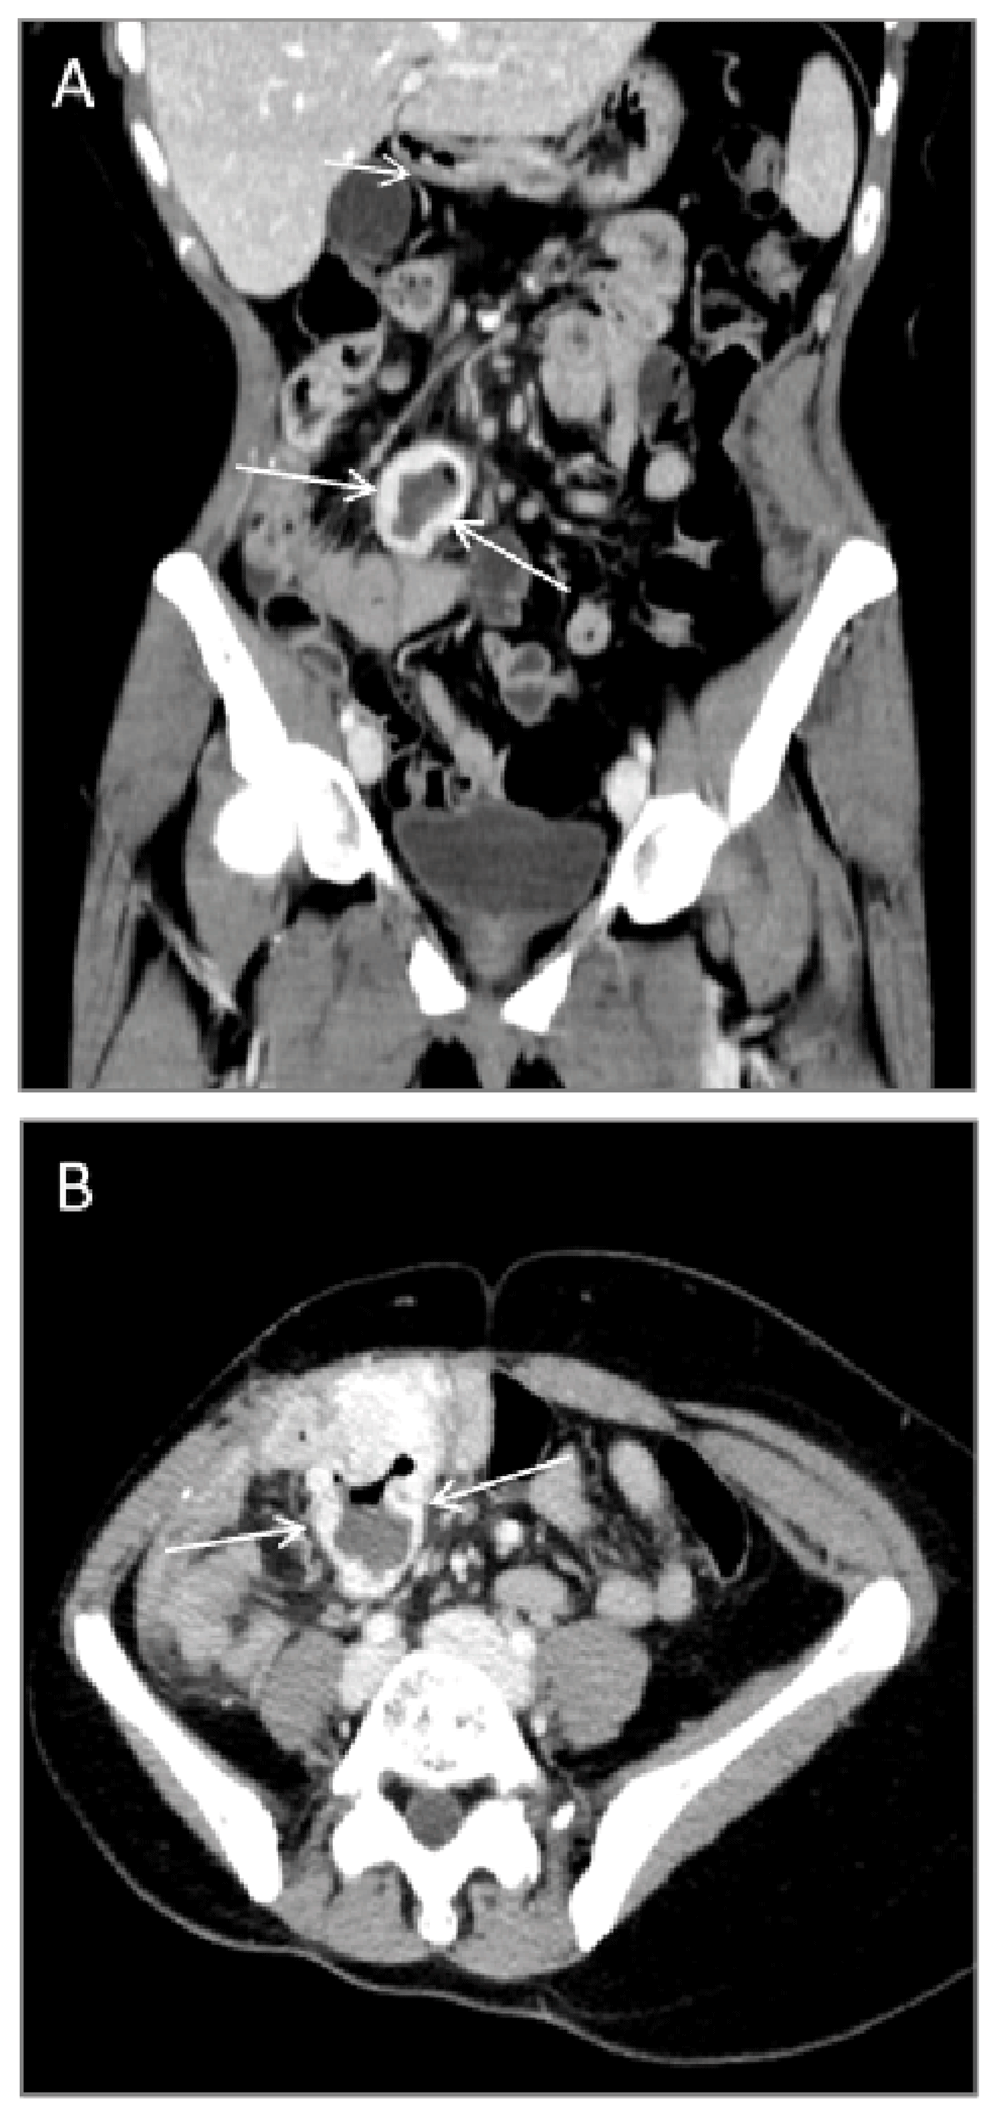

Ileus was initially suspected, and an abdominal CT scan was performed, showing a 3 × 5 × 4 cm mass in the small intestine. The imaging report described, that the lesion was composed of a solid and a necrotic portion plus an air-filled space (Figure 1), which lead to the tentative diagnosis of an underlying Meckel’s diverticulitis. A diagnostic laparoscopy was initiated, but converted to an open ileocecal resection with a primary anastomosis, as a tumor in the terminal ileum was discovered. There was no sign of intestinal perforation.

Grossly, the specimen consisted of a cecal pole that included the appendix and the distal 40 cm of the terminal ileum bound together in a conglomerate (Figure 2). 10 cm from the proximal resection margin a diverticulum-like pouch arising from the ileal wall was identified. The lesion contained a solid tumor of firm consistency, that measured 3 (depth) × 5 (width) cm. The cut surface of the tumor elicited heterogeneity with white/grayish areas and focal haemorrhage. The tumor was totally embedded.